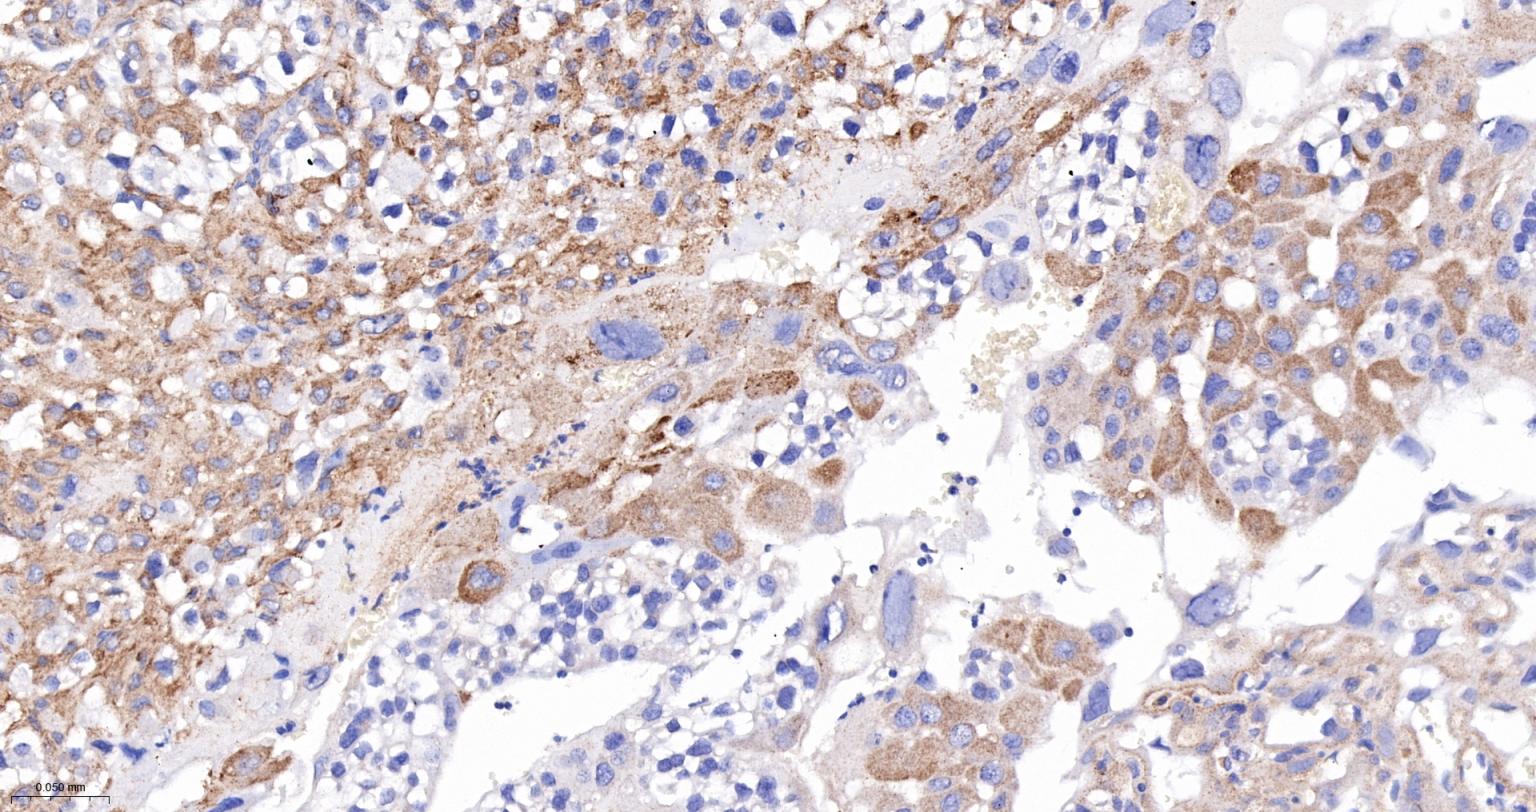

Paraformaldehyde-fixed, paraffin embedded Human Pancreas; Antigen retrieval by boiling in sodium citrate buffer (pH6.0) for 15 min; The section was incubated with VAMP8 Monoclonal Antibody, Unconjugated (bsm-61388R) at 1:200 overnight at 4°C, followed by conjugation to the bs-0295G-HRP and DAB (C-0010) staining